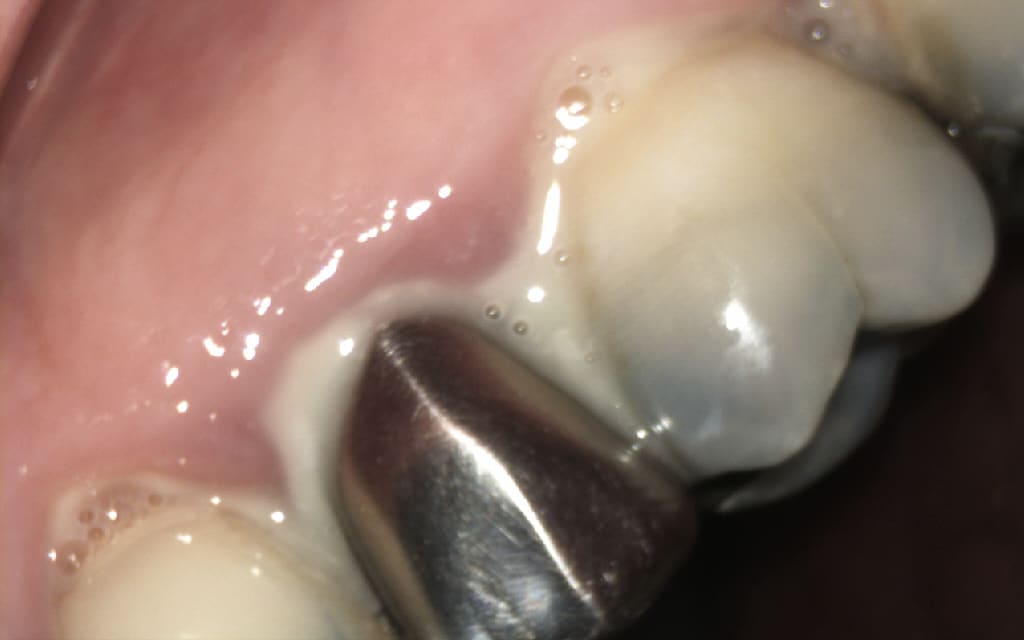

Ce patient avait une grosse infection sur la 25 et malgré plusieurs séance d hca cela ne cicatrisait pas. j, ai donc décidé avec lui de tenter une ERI.

voici la radio de contrôle du patient a 2 ans.